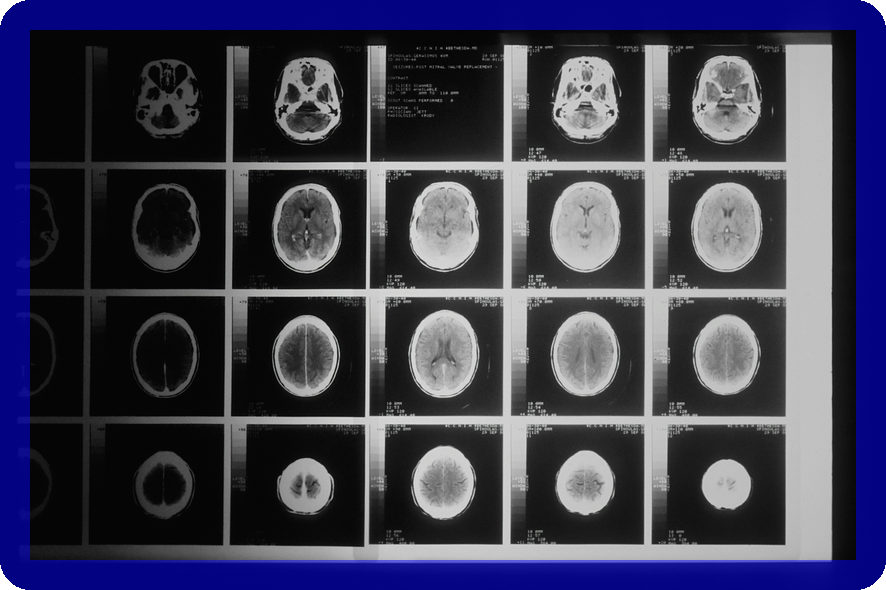

척수종양은 척수 내부 또는 주변에 생기는 종양을 의미하며, 신경계에 심각한 영향을 미칠 수 있습니다. 이 글에서는 척수종양의 주요 종류인 원발성 종양, 내재성 종양, 전이성 종양에 대해 자세히 살펴보겠습니다. 이를 통해 척수종양에 대한 전반적인 이해를 높일 수 있습니다.

척수종양의 치료는 종양의 종류와 위치에 따라 달라지며, 적절한 진단과 치료가 필수적입니다. 본 섹션에서는 효과적인 치료 방법에 대해 자세히 알아보겠습니다.